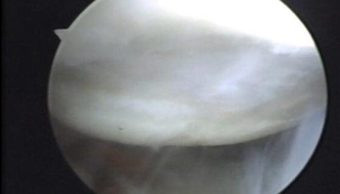

Durante la artroscopía se comprueba la existencia de la lesión de Hill Sacks, la cual es una lesión osteocondral por las luxaciones anteriores que ha sufrido el paciente